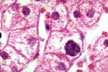

Binucleated hepatocytes

Fig 64 - These binucleated cells increase in accelerated liver cell renewal following an injury.Their presence, therefore, has a diagnostic significance.This slide shows many binucleated hepatocytes in a liver with obvious lobular inflammation.The binucleation is the result of nuclear division not followed by cytoplasmic division.